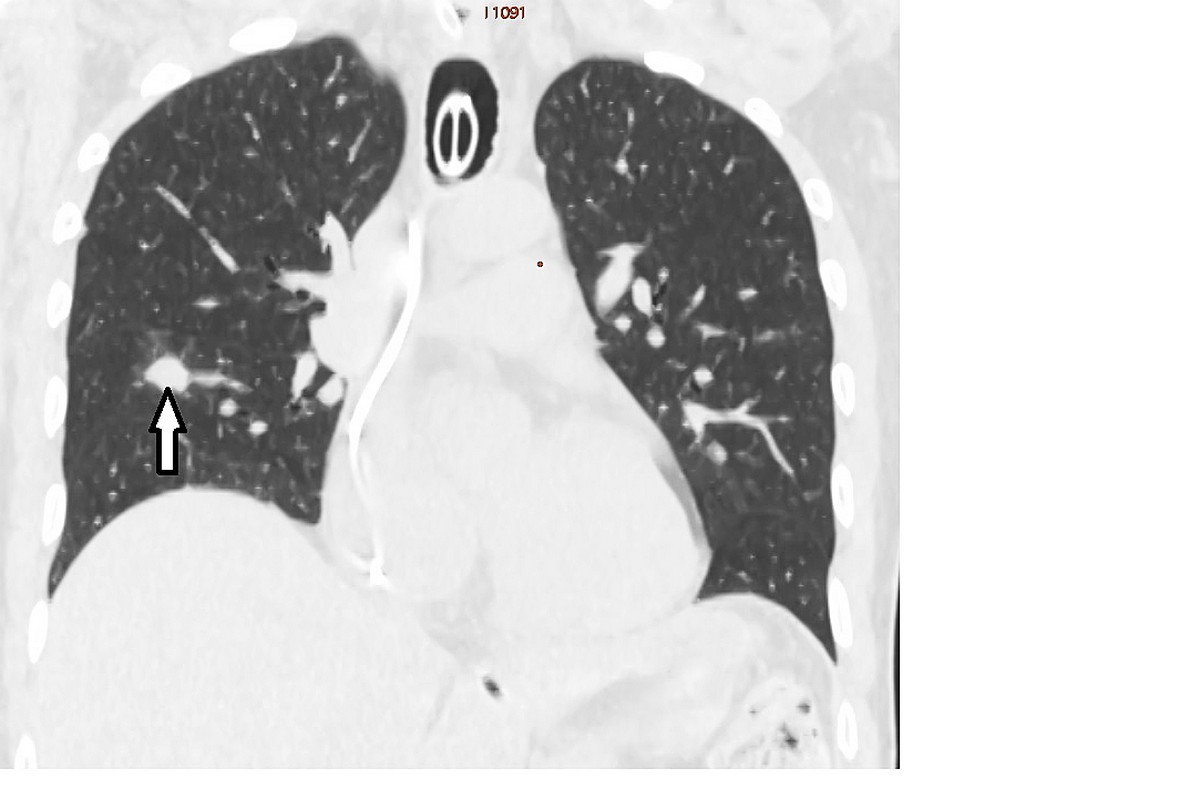

Podczas zabiegu przez skórę wprowadzono igłę, której końcówkę umieszczono w guzku przerzutowym i zniszczono go za pomocą wysokiej temperatury. Zabieg przebiegł bez powikłań. Pacjent planowo będzie wypisany do domu 1-2 dni po zabiegu.

Autor zdjęcia: Grzegorz Rosiak WUM